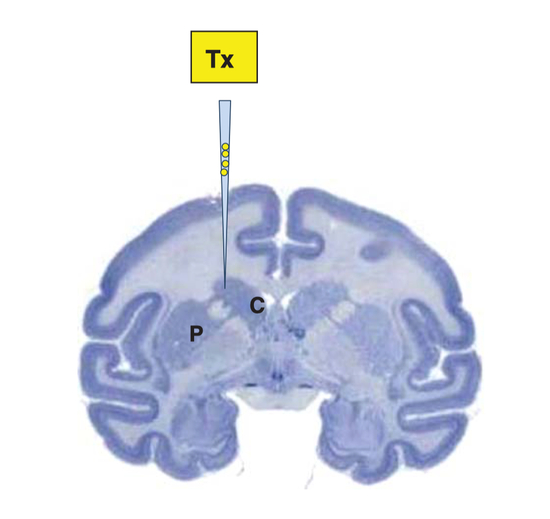

移植的位置

既然猴子也没啥问题了,就开始做人的临床试验了。

2017年,科学家用同样的方式将120个带有猪脑细胞的胶囊植入了病人脑部。一共有18个病程至少5年的老年人参与了实验。

CT下移植入人脑的胶囊位置